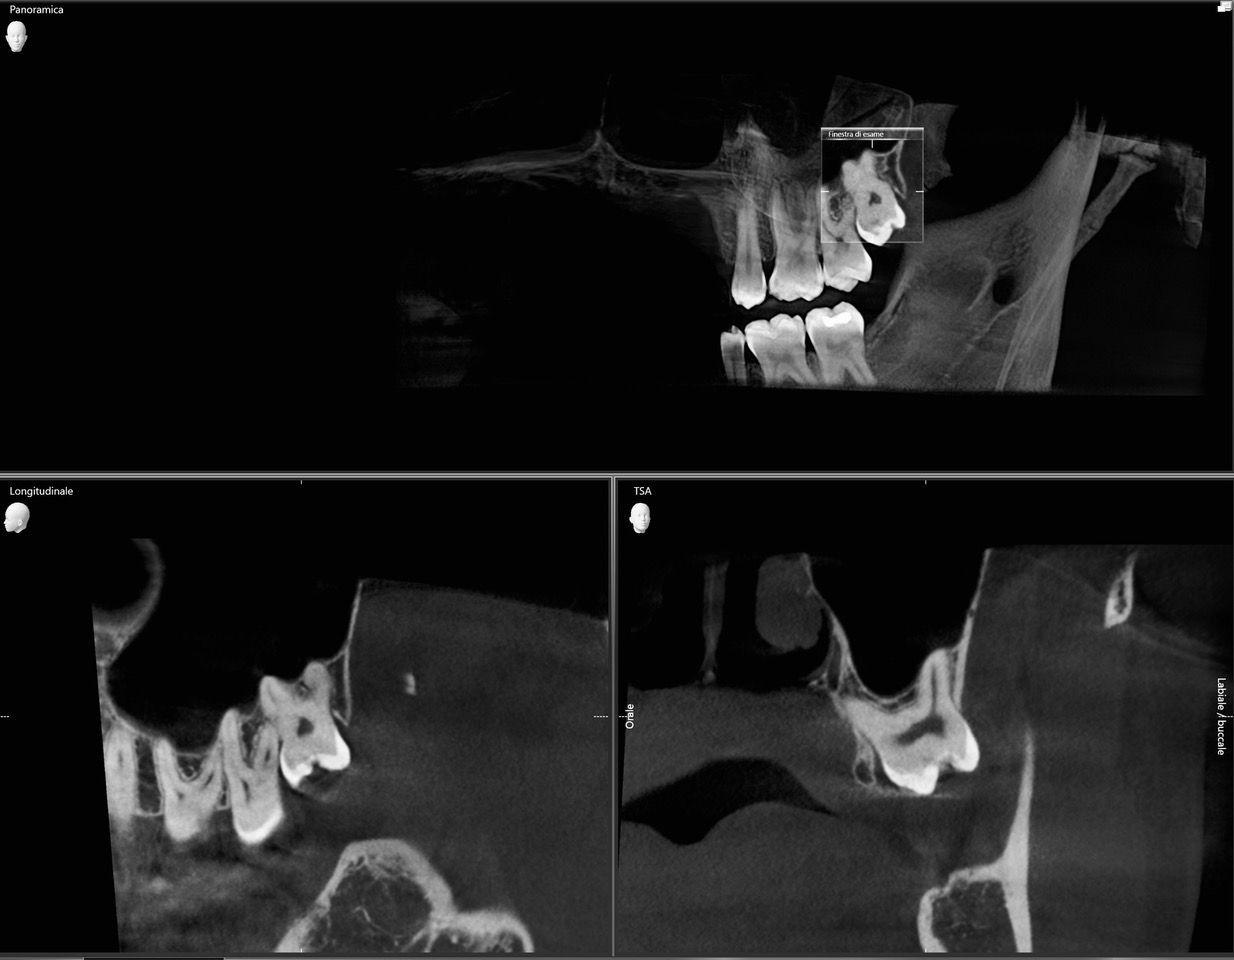

Visione radiografica in 3D